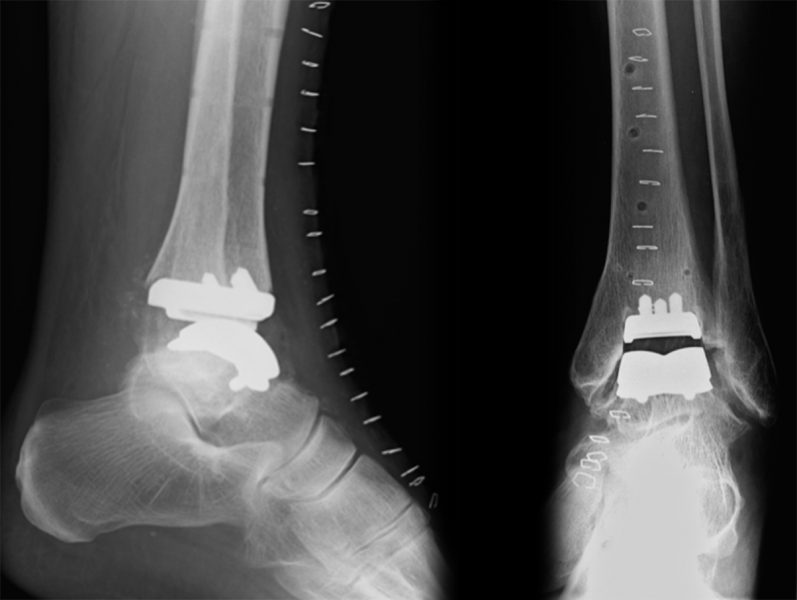

Ausgeprägte Arthrosen des oberen Sprunggelenkes können wir mit einem Kunstgelenk behandeln, Versteifungsoperationen, die sogenannten Arthrodesen des oberen Sprunggelenkes, müssen zunehmend seltener in der Behandlung der Arthrose des oberen Sprunggelenkes durchgeführt werden.

Implantation von Sprunggelenksprothesen